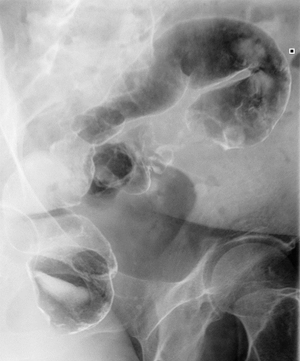

Ирригоскопия